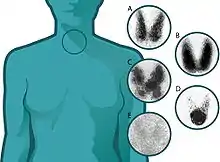

Thyroid scan with Iodine-123 for evaluation of hyperthyroidism.

The normal uptake is between 15 and 25 percent, but this may be forced down if, in the meantime, the patient has eaten foods high in iodine, such as dairy products and seafood.[4] Low uptake suggests thyroiditis, high uptake suggests Graves' disease,[5] and unevenness in uptake suggests the presence of a nodule.